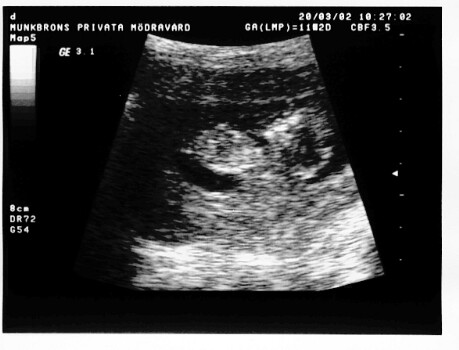

Man kan minsann se

Lite ljusare